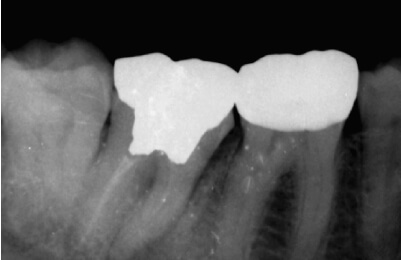

歯髄温存療法症例

-

術前

治療中

顕微鏡下でむし歯を除去

術後

レジン充鎮

矢印部に深いむし歯

封鎖性が良く、

組織の再生を促す

MTAセメントを充填 -

術後2年経過良好

| 主訴 | 冷たいものがしみる。 |

|---|---|

| 治療期間 | 歯髄温存療法1回 ダイレクトボンディング1回 |

| 治療費 |

|

| 治療内容 | マイクロスコープ下でむし歯の除去と、断髄(感染した死神経の一部を除去)を行い、歯髄保護材料(MTA)で封鎖して神経を保存。精密な修復治療により、歯の形態を回復した。 |

| 治療のリスク | 歯髄温存治療が奏効せず、歯髄炎または歯髄壊死になった場合は根管治療が必要になります。 |